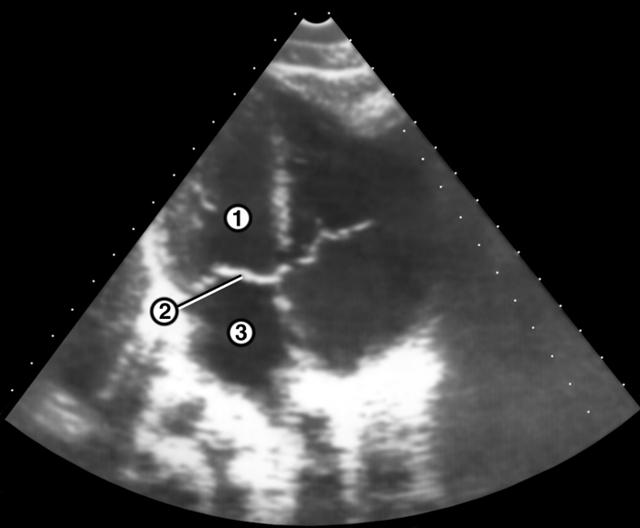

Рис. 2а). Эхокардиограмма в норме.